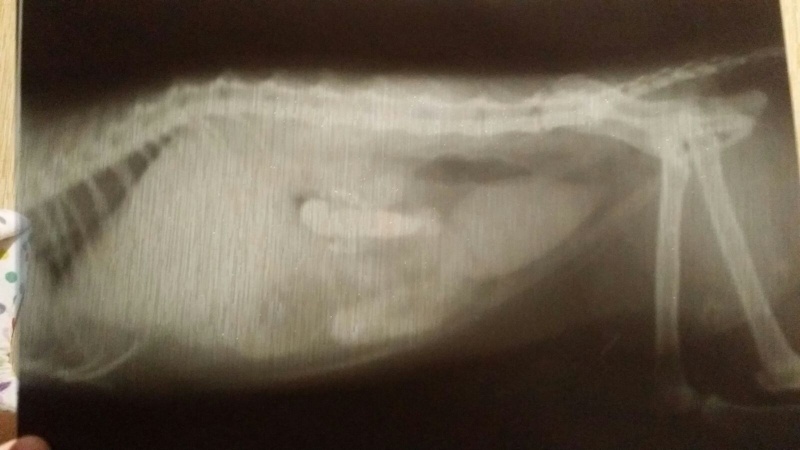

вечером Джуну опять вырвало с барием, Ксюша свозила ее в АС ВЕТ - там поставили серению по весу, чтобы не было рвоты. задала барий повторно в час ночи, утром вчера повезла на ренген. заключение - непроходимость. Как такового предмета не обнаружено, но взвесь бария стоит.

сегодня сделали повторный рентген - барий уже скомковался, но стоит где был, немного продвинулся из-за съеденной пищи. всё.... забрали на операцию.....